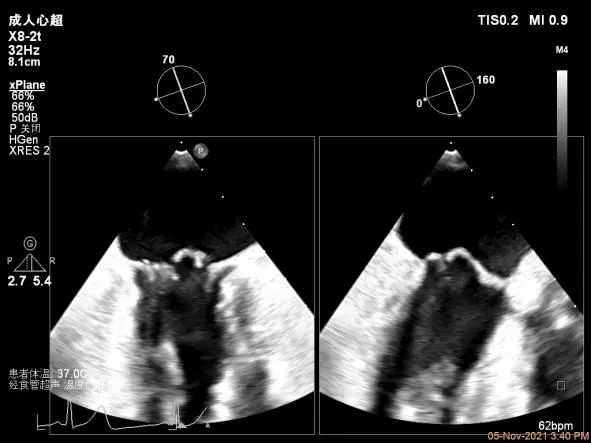

TEE Bicom view:主要脱垂区域为2区

Color-view:返流束主要来源于2区脱垂

A1P1区后叶发育短小,约5.3mm

A2P2区前后叶长度可,为主要脱垂区域,进而制定手术策略: 2区一个长夹子解决脱垂主要病变区域

确定房间隔穿刺点:略靠前,3D视图2点位

穿刺点高度测量:4.37cm

Multivue测量大鞘长度2.34cm